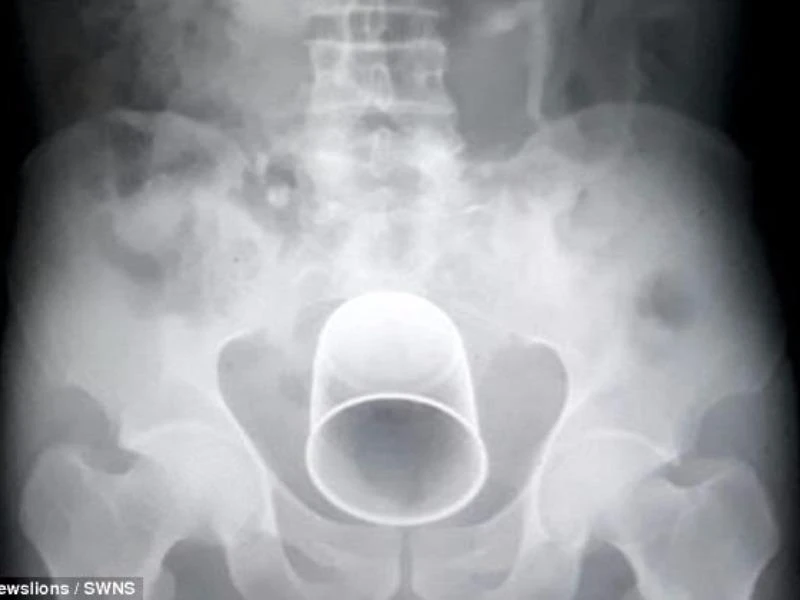

Phim chụp X-quang cho thấy chiếc cốc nằm bên trong cơ thể bệnh nhân. Ảnh: SWNS

Bấy giờ gia đình ông cụ mới đưa ông đến BV tư Sarthak ở Satna, bang Madhya Pradesh, Ấn Độ để điều trị. Sau khi nội soi và chụp X-quang, các bác sĩ ở đây ngỡ ngàng phát hiện ra một vật lạ bên trong bụng ông lão.

"Đó là một chiếc cốc bằng kim loại khá lớn và chúng tôi buộc phải phẫu thuật để lấy nó ra" - BS Sunil Agarwal, Trưởng nhóm điều trị, cho biết.